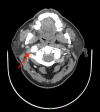

Eagle's syndrome is a rare cause of cervicofacial pain and is due to abnormalities in the stylohyoid process, stylohyoid ligament or lesser cornu of the hyoid bone. Generally, patients affected by Eagle's syndrome present with pain in the lateral or upper neck, angle of the mandible, submandibular space and throat (exacerbated by head movements and/or mastication); foreign body sensation; headache and referred otalgia. A 66-year old gentleman presented with a 36-month history of recurrent pain localising mainly to the right angle of the mandible and radiating to the submandibular triangle. No pathological changes were noted on multiple ultrasound scans. Flexible nasendoscopy revealed a right vocal cord palsy. Initially, the CT scan revealed an abnormality in the stylohyoid complex, and the patient was managed conservatively. Subsequent three-dimensional CT scan noted significant worsening of the abnormality in the stylohyoid complex. Due to progressive nature of the patient's symptoms and progression of stylohyoid complex calcification noted on imaging, the patient was listed for surgery. He underwent partial styloidectomy and vocal cord injection for cord paralysis secondary to impingement on the vagal nerve by the stylohyoid complex. The patient recovered well and denies any ongoing stylalgia. Various cases of Eagle's syndrome have been managed successfully in a conservative manner. However, the authors of this case report suggest that patients with Eagle's syndrome should be monitored closely. A delay in surgical intervention can lead to complications such as complete ossification of the stylohyoid complex and impingement on surrounding structures. This, in turn, increases intra-operative complexity.